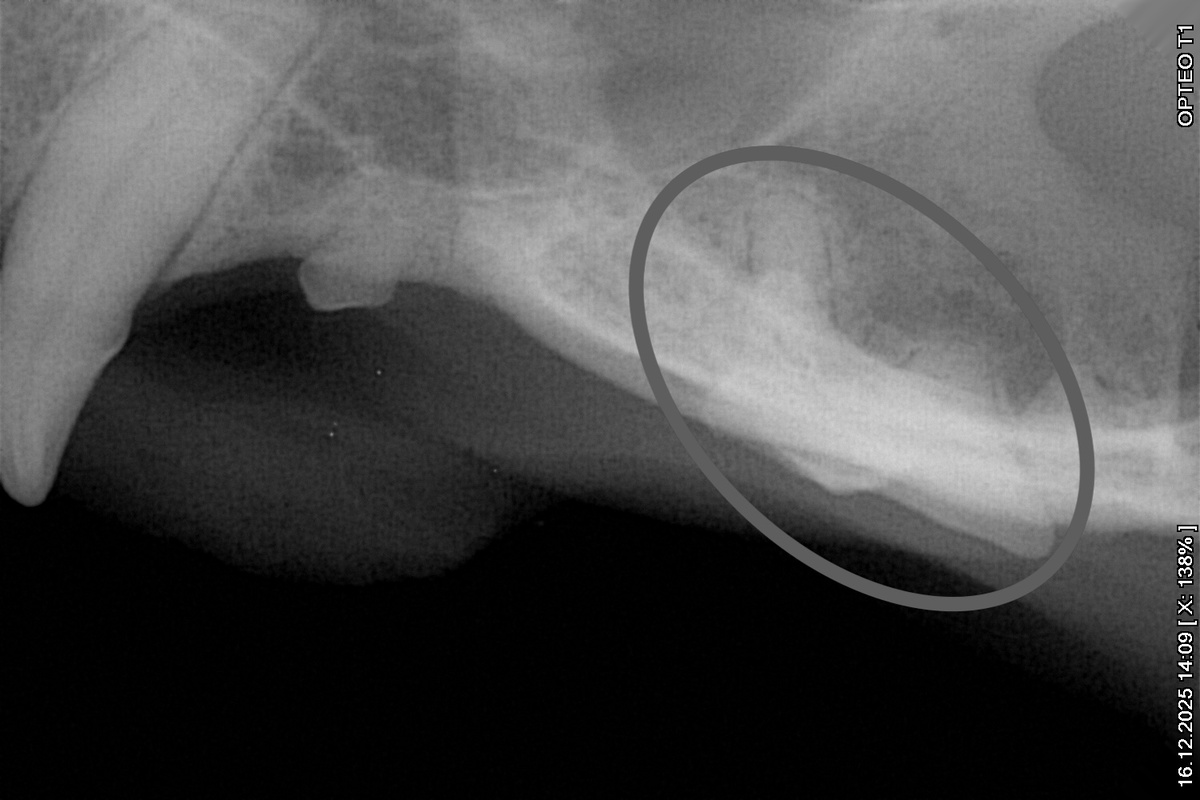

Мне направили кучу снимков дентального рентгена*, всё показали, пригласили на повторный прием через год. Стоматолог была крайне уверена в проведенных вмешательствах и восстановлении, я тоже. Но все равно держала в голове, что может понадобиться приехать повторно в ближайшее время. Послеоперационные риски никто не отменял.

*в ветеринарии это оборудование для метода диагностики, при котором делаются рентгеновские снимки конкретных зубов и прилежащих к ним структур. Только так можно увидеть, что же с корнями зубов там, где точечно усилено воспаление десны... Затронут ли пародонт и насколько – иначе не увидеть при относительно несильном поражении.